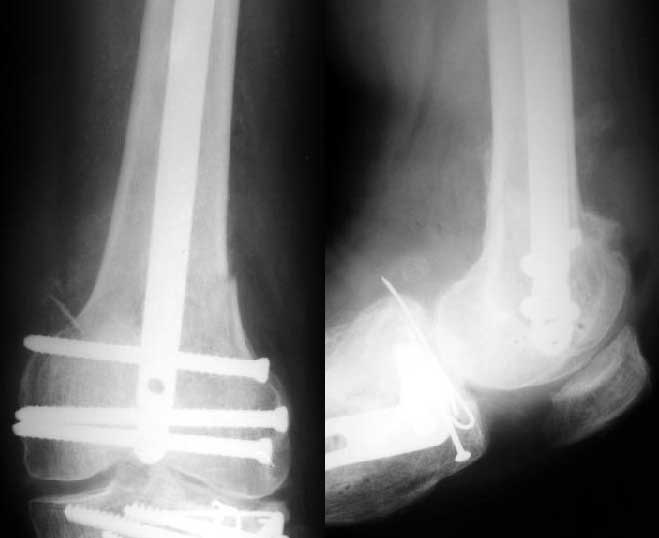

1

Alex>>Since one of nail ends has to be locked without targeting device i

Alex.>> prefer this to be the distal end.

In the supracondylar nail system both the ends are lockable by jig and no free hand technique is needed.

Alex>> Than in the presented case?

I do not see the proximal bolts; I presume they must be at he trochanter level. In a supracondylar nail you are able to see both side bolts in one picture. ( Enclosure)